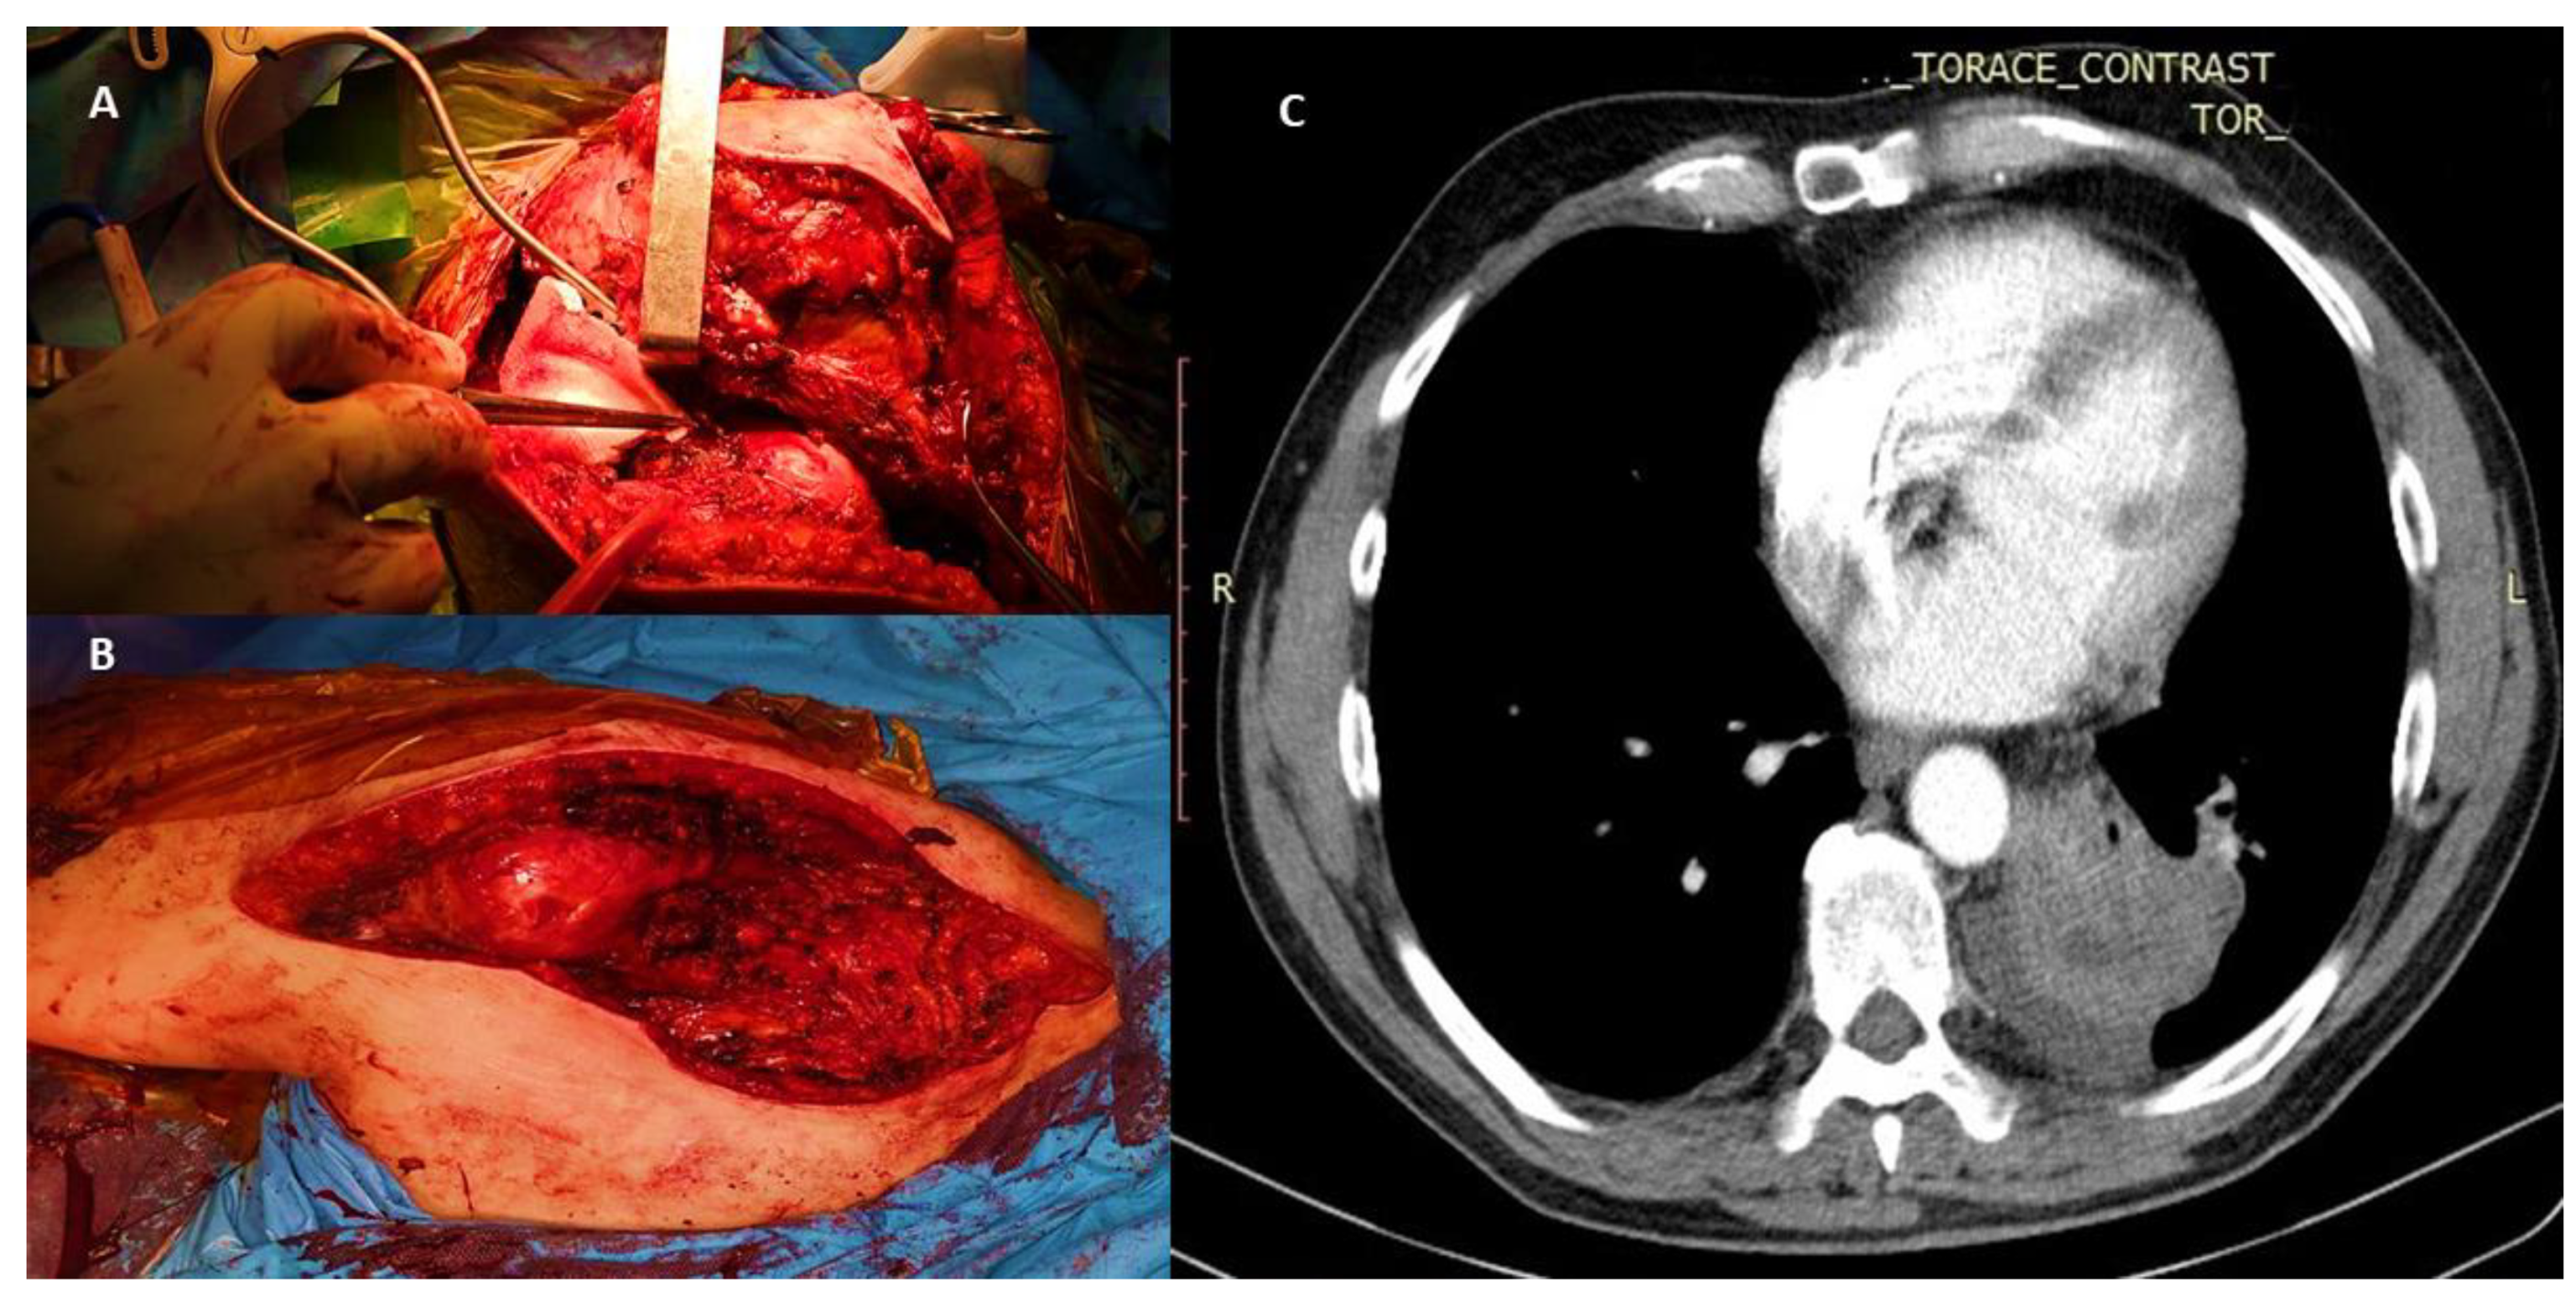

5.2. Resection and Reconstruction of Solitary Bone Lesions in Lung Cancer